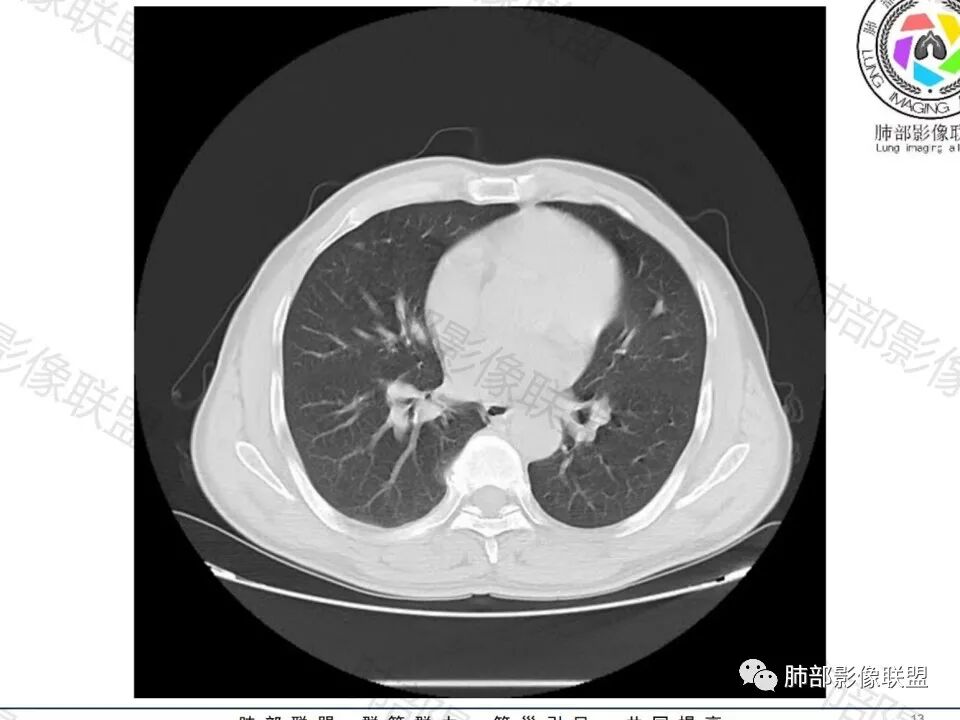

男,60体检发现左肺下叶结节,左肺下叶类圆形结节影,边界清晰,边缘见浅分叶及细短毛刺,病灶内见增粗血管影穿行,相应层面胸膜增厚,双肺另见微小结节影,增强扫描病灶轻度强化,考虑隐球菌,除外腺癌。

老年男性,左肺下叶背段胸膜下孤立结节,整体圆顿,周围有晕,晕中毛刺,似乎支持隐球,但边缘有一囊腔,恶性不能除外!等答案!

左下肺、右中肺均有结节,左下肺病灶比较鼓,边缘有晕,血管弯,持续性强化,考虑腺癌可能,鉴别两处病灶如果一元论,肉芽肿炎 (隐球)

图做的真漂亮!老年男性,双肺多发结节,最大者位于左肺下叶胸膜下,周围有晕,晕中毛刺,边缘有一囊腔,胸膜牵拉,持续强化,考虑隐球,鉴别腺癌。

左肺下叶胸膜下类圆形结节,边缘光滑,周围有晕,晕中有毛刺,周围可见小卫星灶,相邻胸膜增厚,血管进入,右肺中叶可见小结节影,考虑炎性肉芽肿,隐球菌。鉴别腺癌。

老年男性,左肺下叶背段胸膜下结节,边缘毛刺,血管进入,斜裂有牵拉,局部胸膜糊墙,周围有晕,但有一囊腔,首先考虑腺癌,但是右肺中叶及左肺下叶还有其他结节,鉴别隐球菌

病史:男,60岁,体检左下肺结节,肿标阴性;

老年男性,无症状,肺气肿背景

1、炎性结节,多发,类似,晕,隐球菌?

2、恶性:多发:转移瘤?肺癌并多发转移瘤?